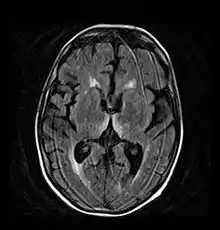

- Axial MRI FLAIR image showing hyperintense signal in the mesial dorsal thalami, a common finding in Wernicke encephalopathy. This patient was nearly in coma when IV thiamine was started, he responded moderately well but was left with some Korsakoff type deficits.

- Axial MRI B=1000 DWI image showing hyperintense signal indicative of restricted diffusion in the mesial dorsal thalami.

- Axial MRI FLAIR image showing hyperintense signal in the periaqueductal gray matter and tectum of the dorsal midbrain.